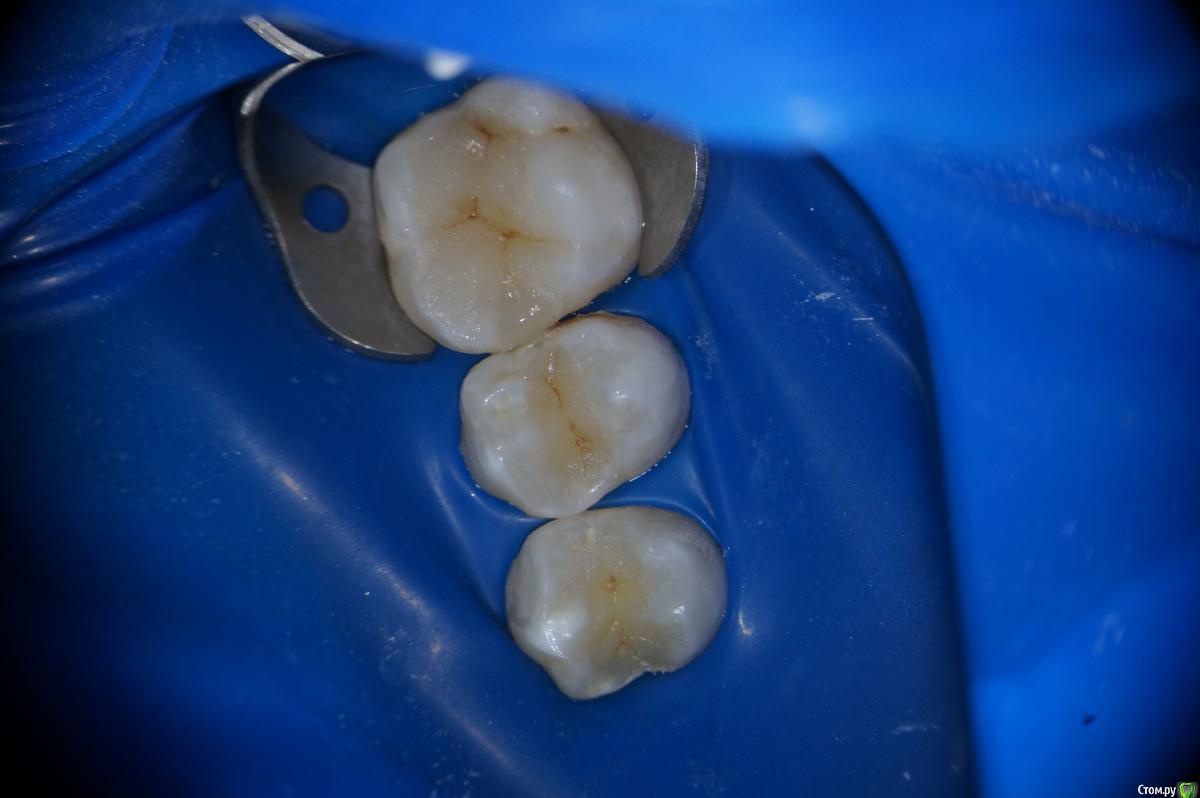

Hans85 Опубликовано 15 января, 2014 Автор Поделиться Опубликовано 15 января, 2014 Сразу скажу что с эндо у меня обстоит лучше чем с реставрациями так что сильно не пинайте.Пациентка страховая,так что речь про вкладки не идет.так сказать возможность тренится в художественной лепке.ЗУбы 26 25 24.На фото 26 уже сделанный. 7 Ссылка на комментарий

Hans85 Опубликовано 14 января, 2015 Автор Поделиться Опубликовано 14 января, 2015 для разбавления эндо чутка занимаюсь художественной лепкой,да Маэстро еще далеко,но будем учиться. 13 Ссылка на комментарий